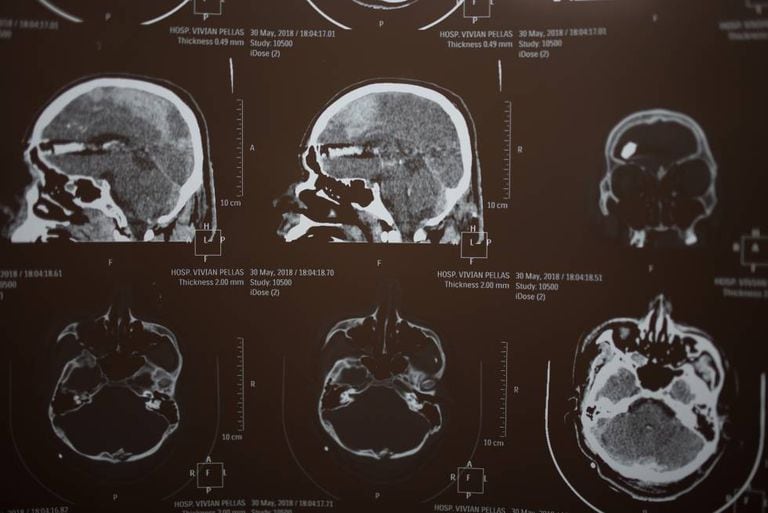

Josefa Esterlina Meza marchava em Managua com centenas de milhares de nicaraguenses em 30 de maio para homenagear as mães das vítimas da repressão que o presidente Daniel Ortega desatou em abril, quando começaram as manifestações que exigem o fim de seu mandato. Josefa participou da chamada Mãe de todas as marchas com seus filhos e não podia imaginar que horas depois ela mesma passaria a fazer parte da lista das mães enlutadas pela violência do Estado. Nessa tarde, quando se comemorava o Dia das Mães na Nicarágua, uma bala tirou a vida de Jonathan Morazán Meza, de apenas 21 anos e estudante de Design Gráfico. “Meu filho foi assassinado pelos paramilitares” diz a mulher. “Foi um franco-atirador”, afirma enquanto mostra as radiografias de Jonathan, que mostram a bala alojada no cérebro, um disparo certeiro.

O relato de Josefa é comovente. “Meu filho foi levado de moto. Isso aparece nos vídeos, é claríssimo como o levantaram, como o carregaram para levá-lo a uma caminhonete. O disparo foi diretamente no cérebro, para matar, foi de um franco-atirador, porque são tiros certeiros. Quando chegou ao hospital nem mesmo pôde falar seu nome. Continuei ligando para seu celular e me atenderam quando já estava internado. Foi aí que soube que era meu filho. Eles me disseram que estava ferido e pensei que havia sido atingido na perna. Fui com seu pai ao hospital. Ele já estava em coma”. O jovem morreu em 1 de junho. Josefa não quis que a autópsia fosse feita. “Não confio, não quero que me digam que morreu de outra coisa, como aconteceu com os outros casos das centenas de jovens que morreram pela repressão do Governo. Mas os médicos me deram o diagnóstico, que afirma que ele morreu por arma de fogo, por um tiro na cabeça”, diz.